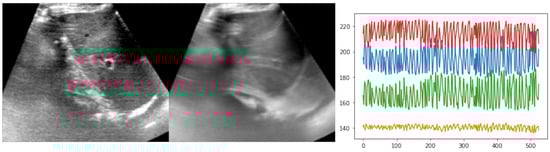

Finally, we also evaluated the two top performing models (from our proposed method and the VoxelMorph baselines) with one another on the CoCoAI dataset. As described above, the challenges of this dataset arise from strong deformation during vein compression, limited contrast of vessels and the potential of confusing artery and vein. Both models were trained with sparse supervision of only the centre points of each vessel across the 21 considered frames. For evaluation, we only used segmentation overlap by propagating the manual multi-class annotation between a fixed and moving frame using the estimated displacments. A comprehensive visual comparison of results for the ETHZ dataset of the two top models is shown in Figure 5. Table 2 shows the quantitative results for training on 300 sequences and testing on 38 held-out sequences. It became clear that the advantages seen in the previous experiments were also supported by a second dataset and our approach outperformed VoxelMorph by a large margin of 7.3% points, and reached a lower standard deviation.

The visual results are shown in Figure 6, along with a plot of the cumulative distribution of Dice accuracy across all 798 validation samples. The temporal averaging of all warped frames in Figure 6b) should ideally have a sharp mean. As expected, this was not fulfilled without registration. The VoxelMorph result also appeared blurry, while our approach found consistent mappings of images and labels. When considering the plausibility of the deformed segmentation, it appeared that, in contrast to our approach, VoxelMorph was not able to extrapolate from the sparse (centre) annotations to dense displacement that aligned all objects with their boundaries as well as the proposed differentiable convex optimisation.

Figure 6. Qualitative results for the CoCoAI dataset. (a) shows two original frames from a compression sequence, (b) across all registrations with the same fixed frame the label probabilities for arteries after registration were averaged, and, ideally, two non-blurry circles should be seen, (c) the cumulative accuracy plot for all compared methods shows the advantage of our approach, (d) an example segmentation propagation (vein in green, arteries in red), shows that VoxelMorph’s deformation was not as plausible as ours.